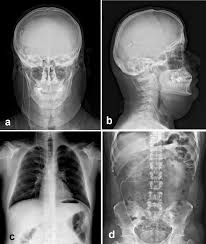

Example Of The Use Of Lodox In Vp Shunt Visualisation In Paediatric Download Scientific Diagram